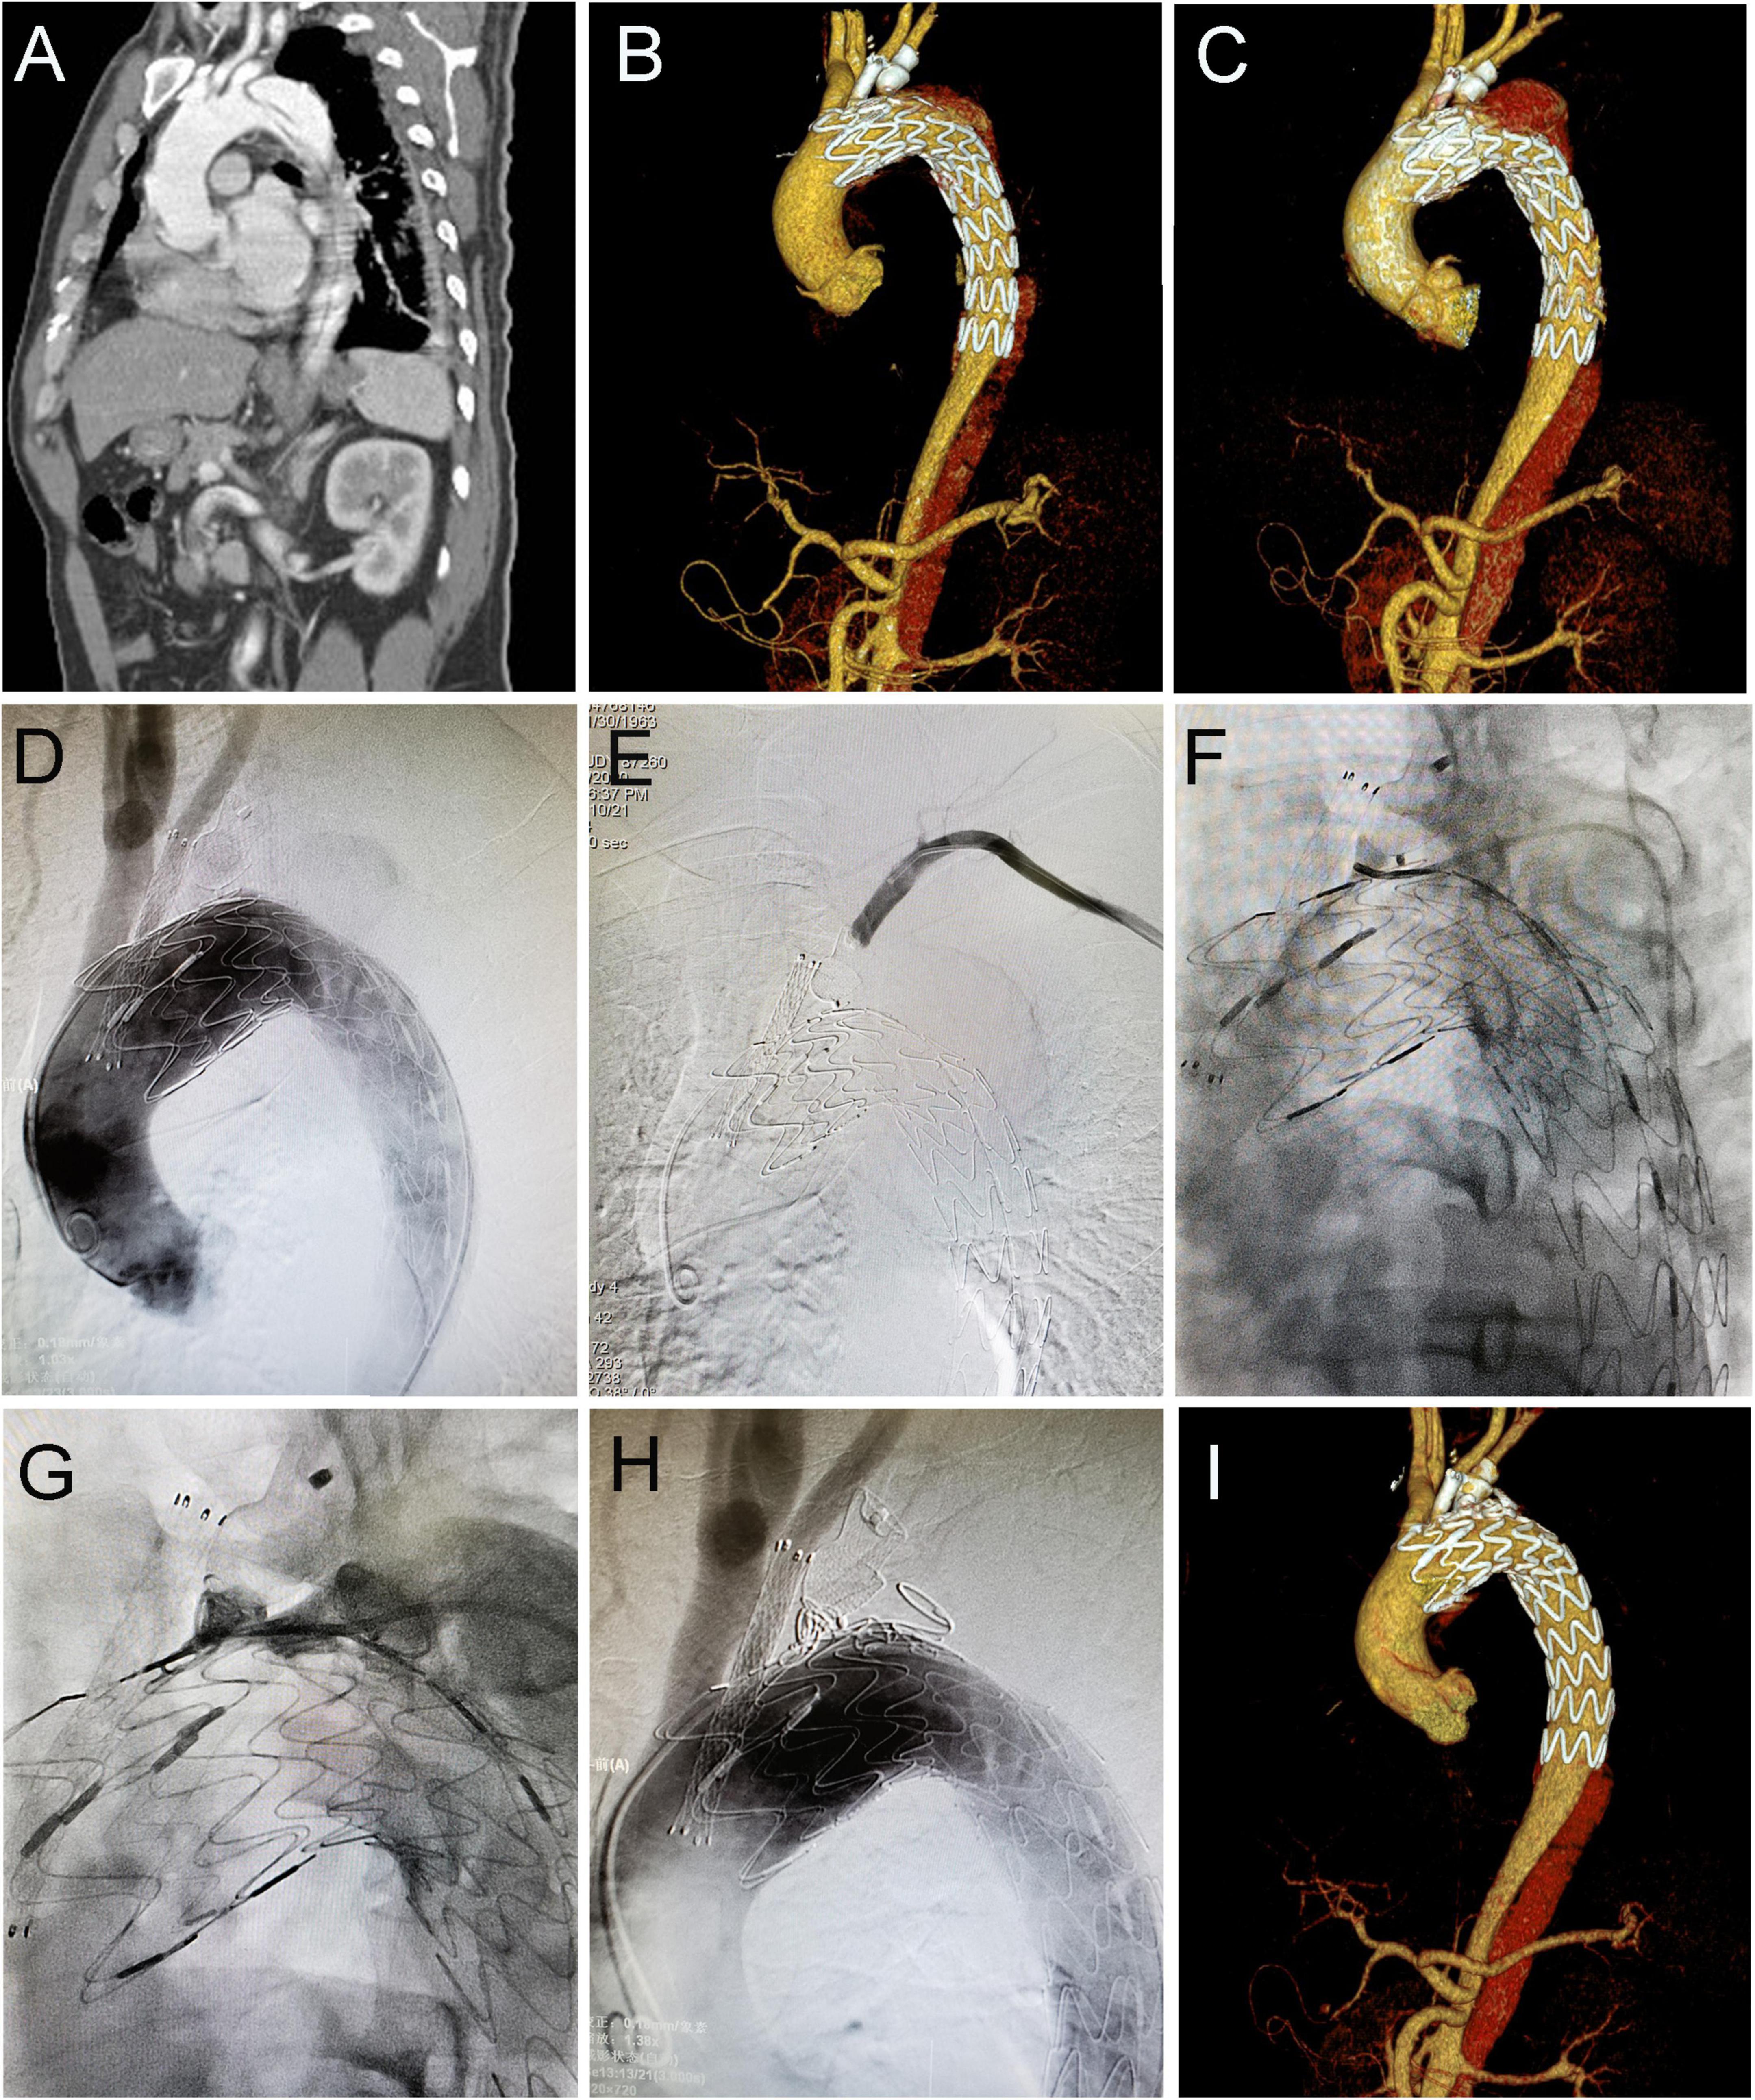

During follow-up, the type IA endoleak disappeared spontaneously in 14 patients, while three patients with progressively increased type IA endoleak received the secondary intervention (two with coil embolization and one with LSA chimney stent angioplasty). As shown in Figure 2, the patient underwent TEVAR with a chimney stent deployed in LCCA and duct occluder in LSA. He showed progressed type IA endoleak after TEVAR and received coil embolization 4 years later, and then the endoleak totally resolved. The remaining 16 patients with persistent type IA endoleak continued to be monitored with close surveillance. Thus, the rate of persistent and re-intervened type IA endoleak was 5.5% (19/345). Type II endoleak from LSA disappeared spontaneously in two patients, two patients with progressed type II endoleak were re-intervened (one with duct occluder and the other with one more stent deployed in LSA and angioplasty). The rest of the two patients with persistent type II endoleak continued to be managed with conservative treatment.

Figure 2. Coil embolization for type IA endoleak 4 years after cTEVAR. Preoperative computed tomography angiography (CTA) showed aortic dissection involving the arch (A). The patient underwent cTEVAR with a chimney stent implanted in LCCA and duct occluder implanted in LSA, and postoperative CTA showed a type IA endoleak (B). The follow-up CTA 4 years later showed the endoleak was significant enlarged (C). With the catheter located in ascending aorta, an angiogram showed contrast could enter the false lumen (D). With the catheter located in LSA, the angiogram showed no contrast entering false lumen (E). With the catheter located in the false lumen, an angiogram showed contrast could enter the aorta (F). After deployment of coils in the false lumen, an angiogram showed contrast could not enter the aorta (G). Post-intervention angiogram (H) and CTA (I) showed the endoleak completely disappeared. cTEVAR, TEVAR with chimney; CTA, computed tomography angiography; LCCA, left common carotid artery; LSA, left subclavian artery; aRSA, aberrant right subclavian artery.